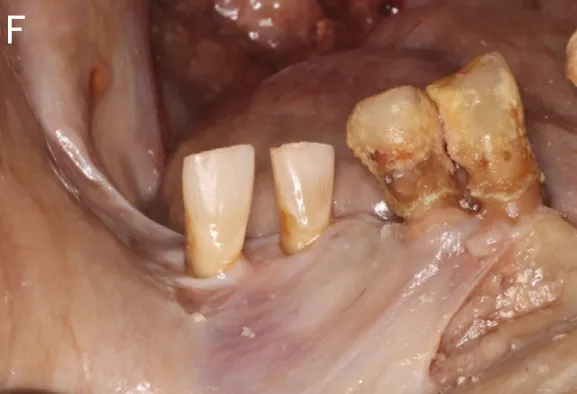

图8:1例右下智齿移植至第一磨牙的临床病例(图引自Tsukiboshi M, Tsukiboshi C, Levin L. A step-by step guide for autotransplantation of teeth. Dent Traumatol. 2023;39 Suppl 1:70-80. doi:10.1111/edt.12819)(A)术前曲面体层片;(B)右下第一磨牙根尖片;(C)右下第一磨牙口内照;(D)右下第一磨牙CBCT矢状位截图;(E)右下第一磨牙远中根CBCT的冠状位截图;(F)右下第一磨牙CBCT轴位截图;(G)3D打印供体牙模型;(H)右下第一磨牙拔除后根尖片;

图10(图引自Chen X, Li J, Zhang Y, Wang H. Navigation-guided autotransplantation: a novel technique for precise and predictable tooth placement. J Oral Maxillofac Surg. 2023;81(4):345-352. doi:10.1016/j.joms.2022.12.005.)结合动态导航技术的自体牙移植:(A)术前口内照;(B)术前根尖片;(C)3D打印供体牙模型试戴;;(D)根尖切除、根管倒预备及倒充填;(E)供体牙就位并固定;(F)术后2个月口内照;(G)术后2个月CBCT矢状位截图;(H)术后2个月CBCT冠状位截图